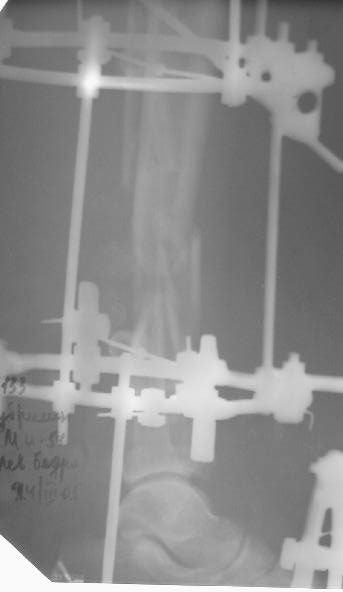

Больному 7 дней назад плита придавила голень стопу. Диагноз Открытый ( 3 б по Каплану) сложный многооскольчатый перелом с выраженным раздроблением н/3 диафиза голени, перелом лодыжек без смещения, перелом основания 5 плюсневой кости с небольшим смещением.

По моему мнению во-первых нужно гешить проблему мягких тканей, для этого провести вторичную и третичную и сколько понадобится обработок при этом удаляя все свободные и инфицированные костные фрагменты - безжалостно и после этого надежное закрытие кожного дефекта с запасом, лучше всего микрохирургический соседистый лоскут . Когда мягкие теани будут готовы в зависимости от размера дефекта можно решить что делать. Лично я предпочитаю замещение дефекта по Илизарову в классическом варианте - остеотомия проксимального отдела тибии и дистальное перемещением с формированием регенерата. Тем более аппарат уже есть. Я бы не стал фиксировать стопу. Судя по снимку дистальный фрагмент достаточно большой, но посмотрим что останется после последней ХО.

А где дефект? Толком не видно.

Согласен с коллегами , что фиксация стопы тут избыточна, и что дефекта не видно.

Больного прооперировал, обработку мягких тканей на голени не стал делать, думаю, некроз по краю швов на голени заживет под струпом (рис 3). На стопе удалил некротические ткани, готовлю ее к аутопластике (рис 2).

На дополнительных снимках итраоперационно видна значительная потеря массы (рис 6 рис 1). Хотя на снимках контрольных после операции вроде дефекта значительного нет. Все же придется, как-то замещать дефект костный на голени, думаю подготовить морально больного к повторной операции костной пластике, после заживления ран.